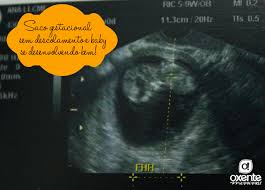

Descolamento Do Saco Gestacional O Que Voce Precisa Saber

Descolamento Do Saco Gestacional Contratempos Na Gravidez